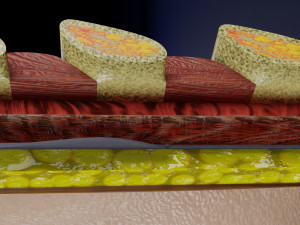

This is a 1:1 scaled model of right breast cut opened in sagittal plane to reveal its internal antomy and histology (schematic). The deeper parts and fascial layers are also depicted to give a very detailed approach to the model. The full layers starting from skin, nipple areola, till intercodtal muscles and ribs are also depicted.

breast mammary gland female chest wall anatomy human medical science reproductive genitalia muscle fascia milk nipple areola subcutaneous fatДо даного товару немає коментарів.